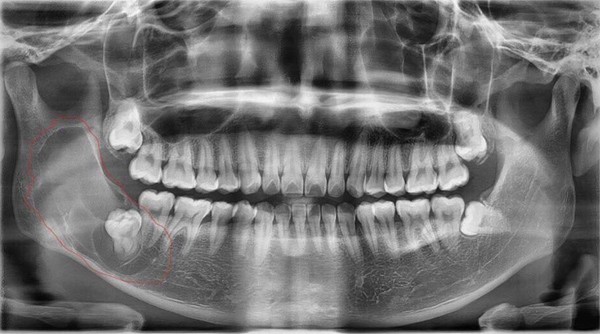

Thời gian gần đây, nam thanh niên thường xuyên thấy đau góc hàm bên phải, nghĩ rằng mình mọc “răng khôn”. Tuy nhiên khi thăm khám trên lâm sàng, bác sĩ không phát hiện bất thường nên chỉ định cho bệnh nhân chụp X-quang.

Kết quả cho thấy, bệnh nhân bị nang răng sừng hoá (hay còn gọi nang răng sinh sừng). Trường hợp bệnh nhân này nang rất lớn, phát triển từ răng số 7 lan lên tới tận xương hàm trên.

Ngày 4/6, BS Thái trực tiếp phẫu thuật cắt bỏ toàn bộ khối nang cho bệnh nhân, kích thước hơn 5 cm. Hiện tại, sức khoẻ bệnh nhân đã ổn định.